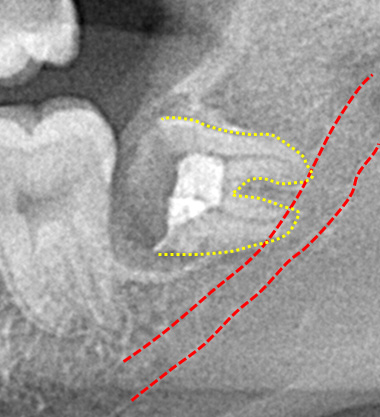

パノラマレントゲン撮影で得られる画像は2次元のため、下顎神経の走行や上顎洞と歯の詳細な位置関係を知るのが難しい場合があります。

CT像では歯の生え方や神経の走行、上顎洞との位置関係などを3次元で確認することができるため、より正確な診断が可能です。主治医が総合的に判断しCT撮影を提案された場合はより安全な抜歯のために受けることをお勧めいたします。また患者様のご希望でも撮影は行いますのでお申しつけください。

親知らずの歯根の先端と下顎神経が近接している場合は2回に分けて抜歯を行うことがあります。まず、親知らずを2分割して頭の部分を抜きます。その後しばらく期間をおいて、のこる歯根の部分が頭を抜いたスペースに移動したのを確認して抜きます。

このように2回に分ける事で安全な抜歯が可能です。

まず歯冠を切除し、疼痛がでないよう、冠部歯髄を除去してネオダイン(歯髄の鎮痛鎮静、象牙質の消毒、覆髄)を填入します。その後、粘膜骨膜弁にて完全閉鎖を行います。以下に処置の流れを示します。

歯冠切除量と歯根の移動量の結果です。術前の智歯(親知らず)の幅径に対して計測した智歯の長径の割合は1.21ポイント、術後は1.10ポイントで有意に差を認めました。数ヵ月待機することにより歯根は有意に近心側に移動していることを認めました。